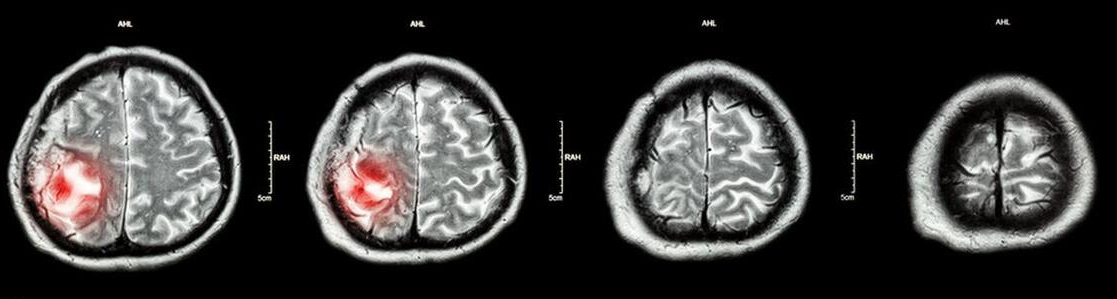

2、影像学检查:头颅CT能快速发现脑部是否有明显的占位性病变;而磁共振成像(MRI)对软组织的分辨力更高,能更清晰地显示肿瘤的位置、大小、形态以及与周围组织的关系,是诊断脑肿瘤的重要手段。